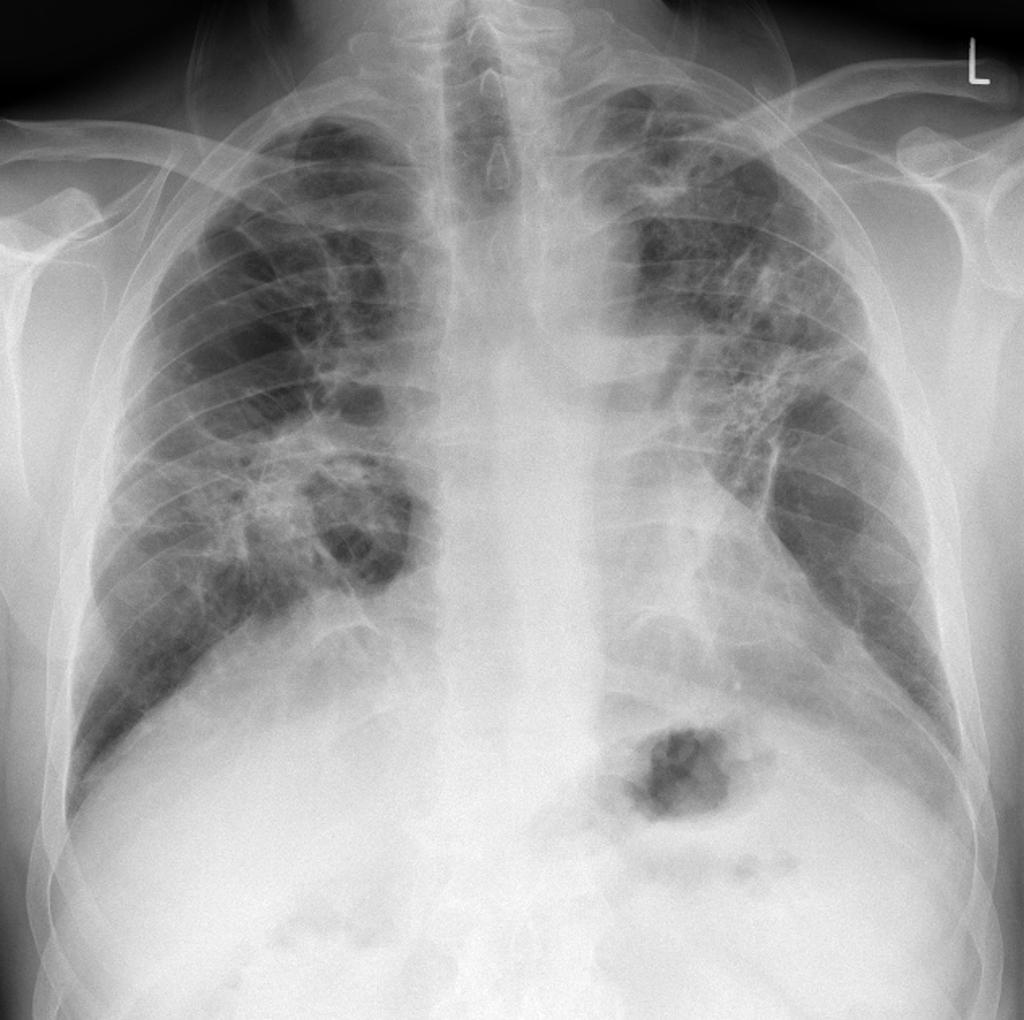

_右肺纖維化真實案例胸片